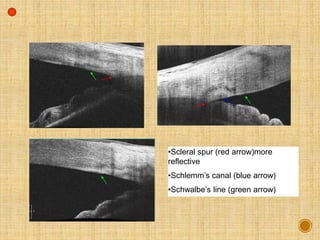

Scleral spur is more reflective

Ciliary body is less reflective

•Scleral spur (red arrow)more

reflective

•Schlemm’s canal (blue arrow)

•Schwalbe’s line (green arrow)